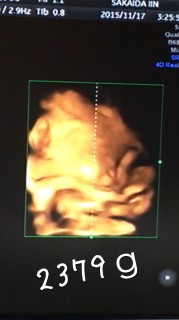

2379gの男の子です。 順調だとの事でパパと早く会いたいね~って毎日言ってます^_^; 無事に産まれてきてくれることを願ってます(o^^o)